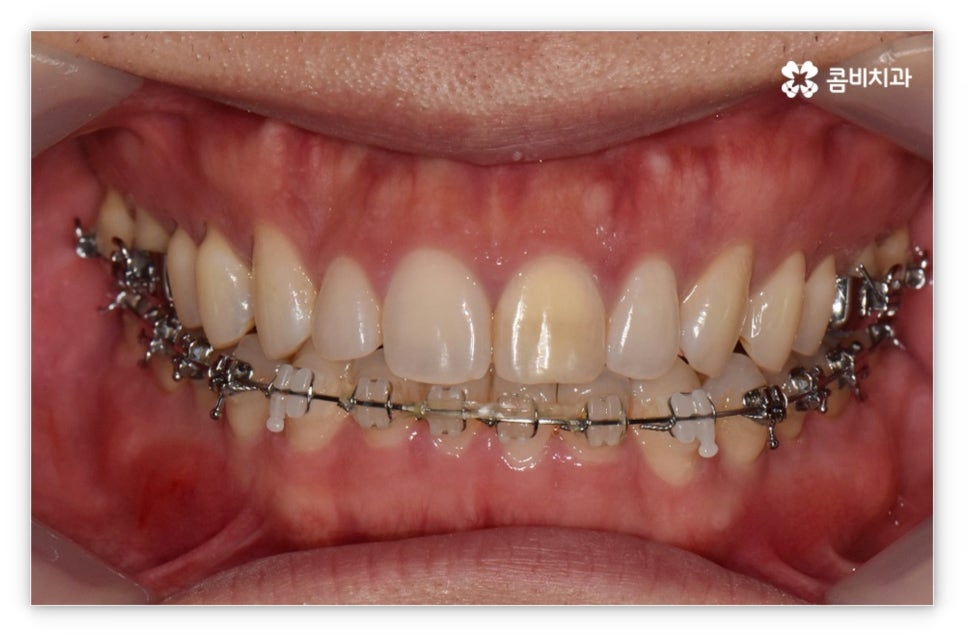

살펴본 바와 같이 앞니설측교정 의 장점에도 불구하고 아랫니 부분은 장치가 혀에 닿게 되기 때문에 환자분들께서 불편함을 느낄 수 있고 혹시라도 혀가 브라켓에 잘못 쓸리거나 눌렸을 때 통증이 발생할 수도 있으며 발음이 불분명해지는 문제가 생길 수 있는데요. 이러한 이유로 앞니설측교정 에 대해서 고민이 되시는 분들은 윗니 부분은 설측으로, 아랫니 부분은 일반 교정처럼 순측으로 진행하는 콤비 교정에 대해서 알아보시면 좋을 거예요. 위의 사진에서 살펴보실 수 있는 경우가 바로 이렇게 콤비 교정으로 진행한 환자분의 케이스인데 아랫니의 경우 보통 입술에 가려 별로 드러나지 않는 데다가 치아 색상인 세라믹 재질로 된 브라켓을 이용하기 때문에 설측 교정과 비교해도 심미성이 크게 떨어지지 않는다는 것을 알 수 있어요. 콤비 교정의 경우 설측 교정보다 비용적인 부담도 줄일 수 있으니 각 장치에 대한 장단점을 의료진분들과 충분히 상담하셔서 자신에게 맞는 장치를 선택하시면 좋을 거예요.